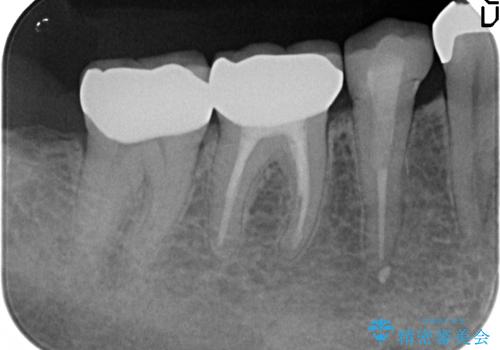

右下6は神経が死んでいたため根管治療を行い、オールセラミッククラウンによる補綴を行いました。

右下7は冷たいものがしみていたため、銀歯を除去後、オールセラミッククラウンによる補綴を行いました。

今回用いたオールセラミッククラウンはジルコニアフレームという白い素材の上にセラミックを盛っているため、審美性が非常に高いのが特徴です。

また、ジルコニアは人工ダイヤモンドの材料にも使われているほど高い強度を持っており、そのためオールセラミッククラウンは審美性だけでなく、奥歯やブリッジの補綴も可能とするクラウンです。